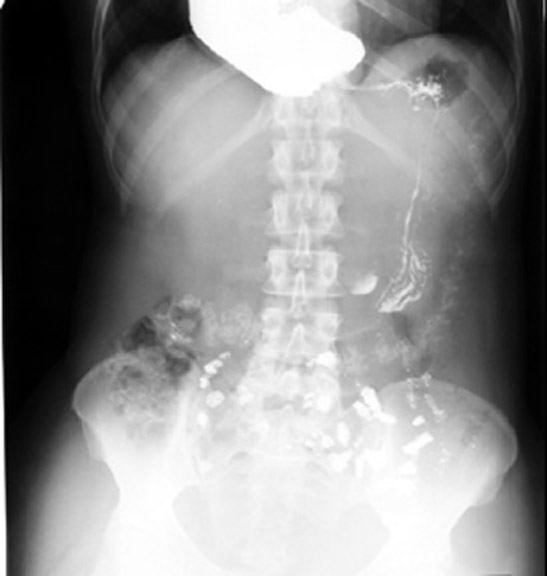

Inlet to outlet shadow in the mediastinum to the right of the mid-line is due to esophageal dilatation (achalasia cardia in this case) and dissecting aneurysm on the left.

• Inhomogeneous cardiac density

• Right sided inlet to outlet shadow

• Barium swallow: Dilated esophagus

This is a case of achalasia cardia.